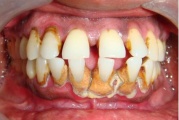

Krooniline parodontiit

Krooniline parodontiit on mikroobide poolt põhjustatud hammaste tugikudede põletik, mille tulemusena tekib progresseeruv alveolaarluu (nähtav röntgenograamil) ja periodontaalligamendi destruktsioon, igemetaskute moodustumine, igeme retsessioon või mõlemad kahjustused kombineeritult. Loe edasi »

- igemed veritsevad (19)

- igemed punetavad (21)

- ige on paistes (mädapunn)

- igemed on tursunud/vohavad (17)

- igemepiir on taandunud (3)

- igemepealne hambakivi (5)

- igemealune hambakivi (4)